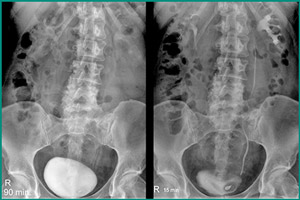

Техника проведения различается в разных методиках. При микционной цистографии органы фотографируются в момент опорожнения и после мочеиспускания. При нисходящем методе после введения препарата ожидают, пока через почки начнет выделяться контрастное вещество и пузырь полностью заполнится жидкостью. Снимки необходимо делать не ранее, чем через полчаса после введения вещества.

Снимки цистографии мочевого пузыря у женщин/мужчин отличаются от детских изображений. После рождения орган ребенка находится выше, но по мере физиологического развития опускается к лобковому сочленению. У подростков и взрослых расположение мочевыделительной системы уже одинаковое. Учитывая эту анатомическую особенность, только уролог может отличить врожденный дефект от нормы.

На снимке цистографии контрастная жидкость имеет белый цвет. При отсутствии аномалий стенки пузыря имеют ровную контурную линию с двумя небольшими выпуклостями внутрь мочеточников. Форма органа зависит от возраста ребенка. Длина уретры у новорожденных девочек составляет 10 мм, а у мужчин – 50 мм. К 16-летию эти значения соответствуют 3,5 см и 16 см.

На снимке цистографии дивертикулы видны в виде выступлений внутрь стенки пузыря. При свищах и разрывах контраст протекает в брюшную полость.

Камень проявляется темным пятном внутри органа, которое всегда смещается при смене положения тела. Опухоль и киста не окрашиваются и не сдвигаются. При раздвоении мочевого пузыря видно 2 белых пятна.